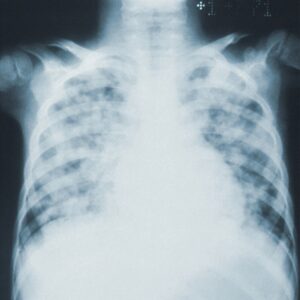

What is the Most Common Presenting Symptom of Malignant Mesothelioma?

Malignant mesothelioma is a rare but aggressive form of cancer that primarily affects the lining of the lungs, abdomen, or heart. This disease is most commonly associated with asbestos exposure,…